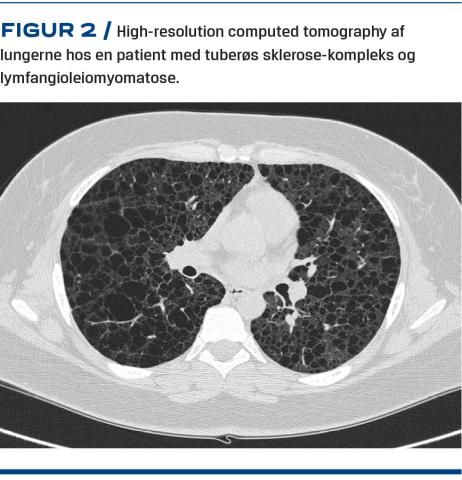

Hypomelanotiske maculae på huden er ligeledes et hyppigt debutsymptom, som ses hos over 90% i løbet af de første leveår. Senere forekommer der angiofibromer i ansigtet, og fra teenagealderen ses subungvale og periungvale angiofibromer [1]. I barne- og teenageårene udvikler ca. 20% cerebrale subependymale kæmpecelleastrocytomer (SEGA) i hjernen, hvilket kan kompliceres med udvikling af hydrocefalus [1, 6]. Angiomyolipomer (AML) ses i nyrerne, og prævalensen øges med alderen fra ca. 10% hos børn under to år til ca. 80% hos voksne over 40 år [1, 7]. AML vokser livet igennem, og hermed stiger risikoen for spontan blødning [8]. Lymfangioleiomyomatose (LAM) i lungerne ses hos ca. 30% af kvinder under 21 år og kan afficere op til 80% af kvinder over 40 år. LAM viser sig ved cyster i lungevævet og kan resultere i nedsat lungefunktion og spontan pneumothorax [1, 9].

Lungemedicin

Alle kvinder over 18 år (eller yngre ved lungesymptomer) henvises til lungefunktionsundersøgelse og high-resolution computed tomography (HRCT) af lungerne (Figur 2). Alle mænd over 18 år (eller yngre ved lungesymptomer) henvises til lungefunktionsundersøgelse og ved nedsat lungefunktion til HRCT, da LAM normalt kun forekommer hos kvinder. Klinisk screening for LAM foretages efterfølgende typisk en gang årligt hos kvinder over 18 år. Ved respiratoriske symptomer foretages der undersøgelse af lungefunktionen, og hvis den er nedsat, suppleres der med HRCT. HRCT overvejes ligeledes hos mænd med respiratoriske symptomer. Kvinder bør undgå østrogen (f.eks. p-piller), som kan øge cysternes progressionshastighed. Hos patienter med moderat-svær lungesygdom eller hurtig progression overvejes behandling med mTOR-hæmmer. Patienterne kan indstilles til lungetransplantation på lige fod med andre lungesyge.